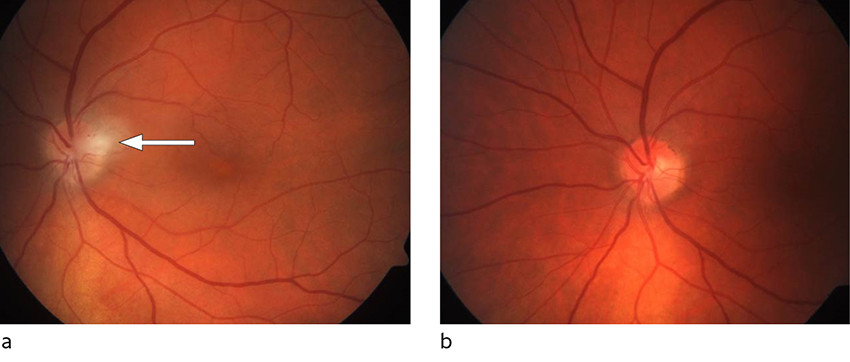

Ophthalmological assessment revealed a normal right eye. Best-corrected visual acuity in the left eye was 0.75, and the patient had no subjective impairment in colour vision. No afferent pupillary defect was described, and the anterior segment was normal. The view of the posterior segment was slightly obscured by cells in the vitreous. Optic disc swelling was observed, with a diffuse infiltrate on the temporal side (Figure 1a).

Unilateral optic disc swelling is suggestive of optic neuropathy, and strengthens suspicion of a demyelinating optic neuritis with involvement of the optic disc. However, there were two 'red flags', or findings that were not typical of demyelinating optic neuritis: the presence of cells in the vitreous and the peripapillary infiltrate (1, 2). These findings led us to consider other possible causes of optic neuritis with optic disc involvement Box 1) ((1, 3).

Six weeks later, the patient was virtually symptom-free. Best corrected visual acuity in the left eye was now 1.25, and the temporal peripapillary infiltrate had disappeared (Figure 1b).